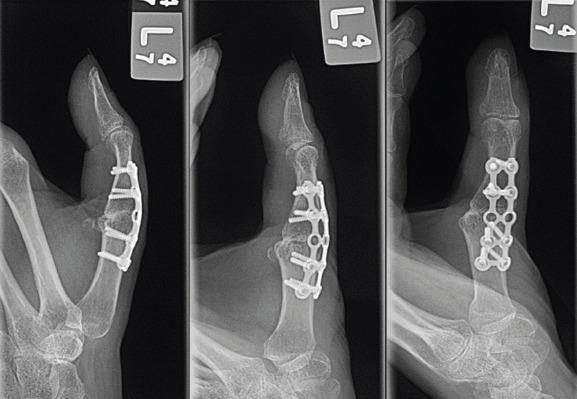

We report a rare case of severe Type 1 thumb boutonniere deformity with IP joint dislocation in a 42-year-old, high-demand female patient with a history of autoimmune diseases. We describe the successful treatment of this severe thumb deformity using MCP arthrodesis and temporary IP joint pinning, which resulted in preserved function and stability. At 1-year follow-up, the patient reported good function of the thumb with no instances of IP joint dislocation.

我们报告了一例罕见的1型拇指纽扣畸形伴IP关节脱位的病例,患者为一名42岁、需求较高且有自身免疫性疾病病史的女性。我们描述了使用MCP关节融合术和临时IP关节穿针固定成功治疗这种严重拇指畸形的过程,该治疗方法保留了拇指的功能和稳定性。在1年的随访中,患者报告拇指功能良好,未出现IP关节脱位的情况。

在先前的文献中,对于严重的拇指纽扣畸形,推荐采用MCP关节成形术联合IP关节融合术,但这可能不适用于年轻、需求较高的患者。外科医生应全面了解每位患者的解剖结构和功能目标,以制定最佳的治疗策略。在该患者群体中,MCP关节融合术和临时IP关节穿针固定的成功体现在随访1年时IP关节活动范围得以维持,且在捏取和抓握活动中未出现脱位。